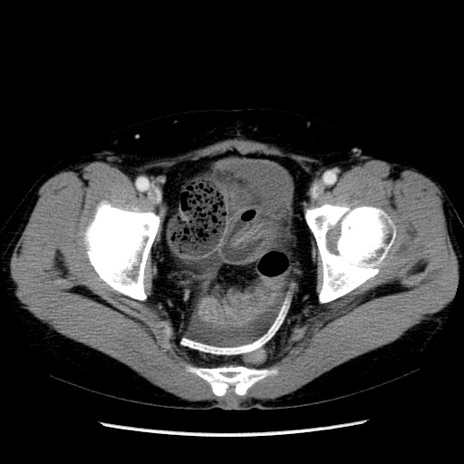

症例6(横断像)

【症例】50歳代女性

【主訴】下腹部痛

【現病歴】本日朝より下痢2回あり。 昼食を食べた後、嘔吐3回、下腹部痛認め、症状軽快せず、当院救急搬送。

【既往歴】卵巣癌術後(8年前に当院で卵巣摘出)

【身体所見】 意識清明、腹部:平坦、腸蠕動音→、やや硬、下腹部自発痛・圧痛あり、反跳痛あり、筋性防御なし。

【データ】WBC 16000、CRP 0.01